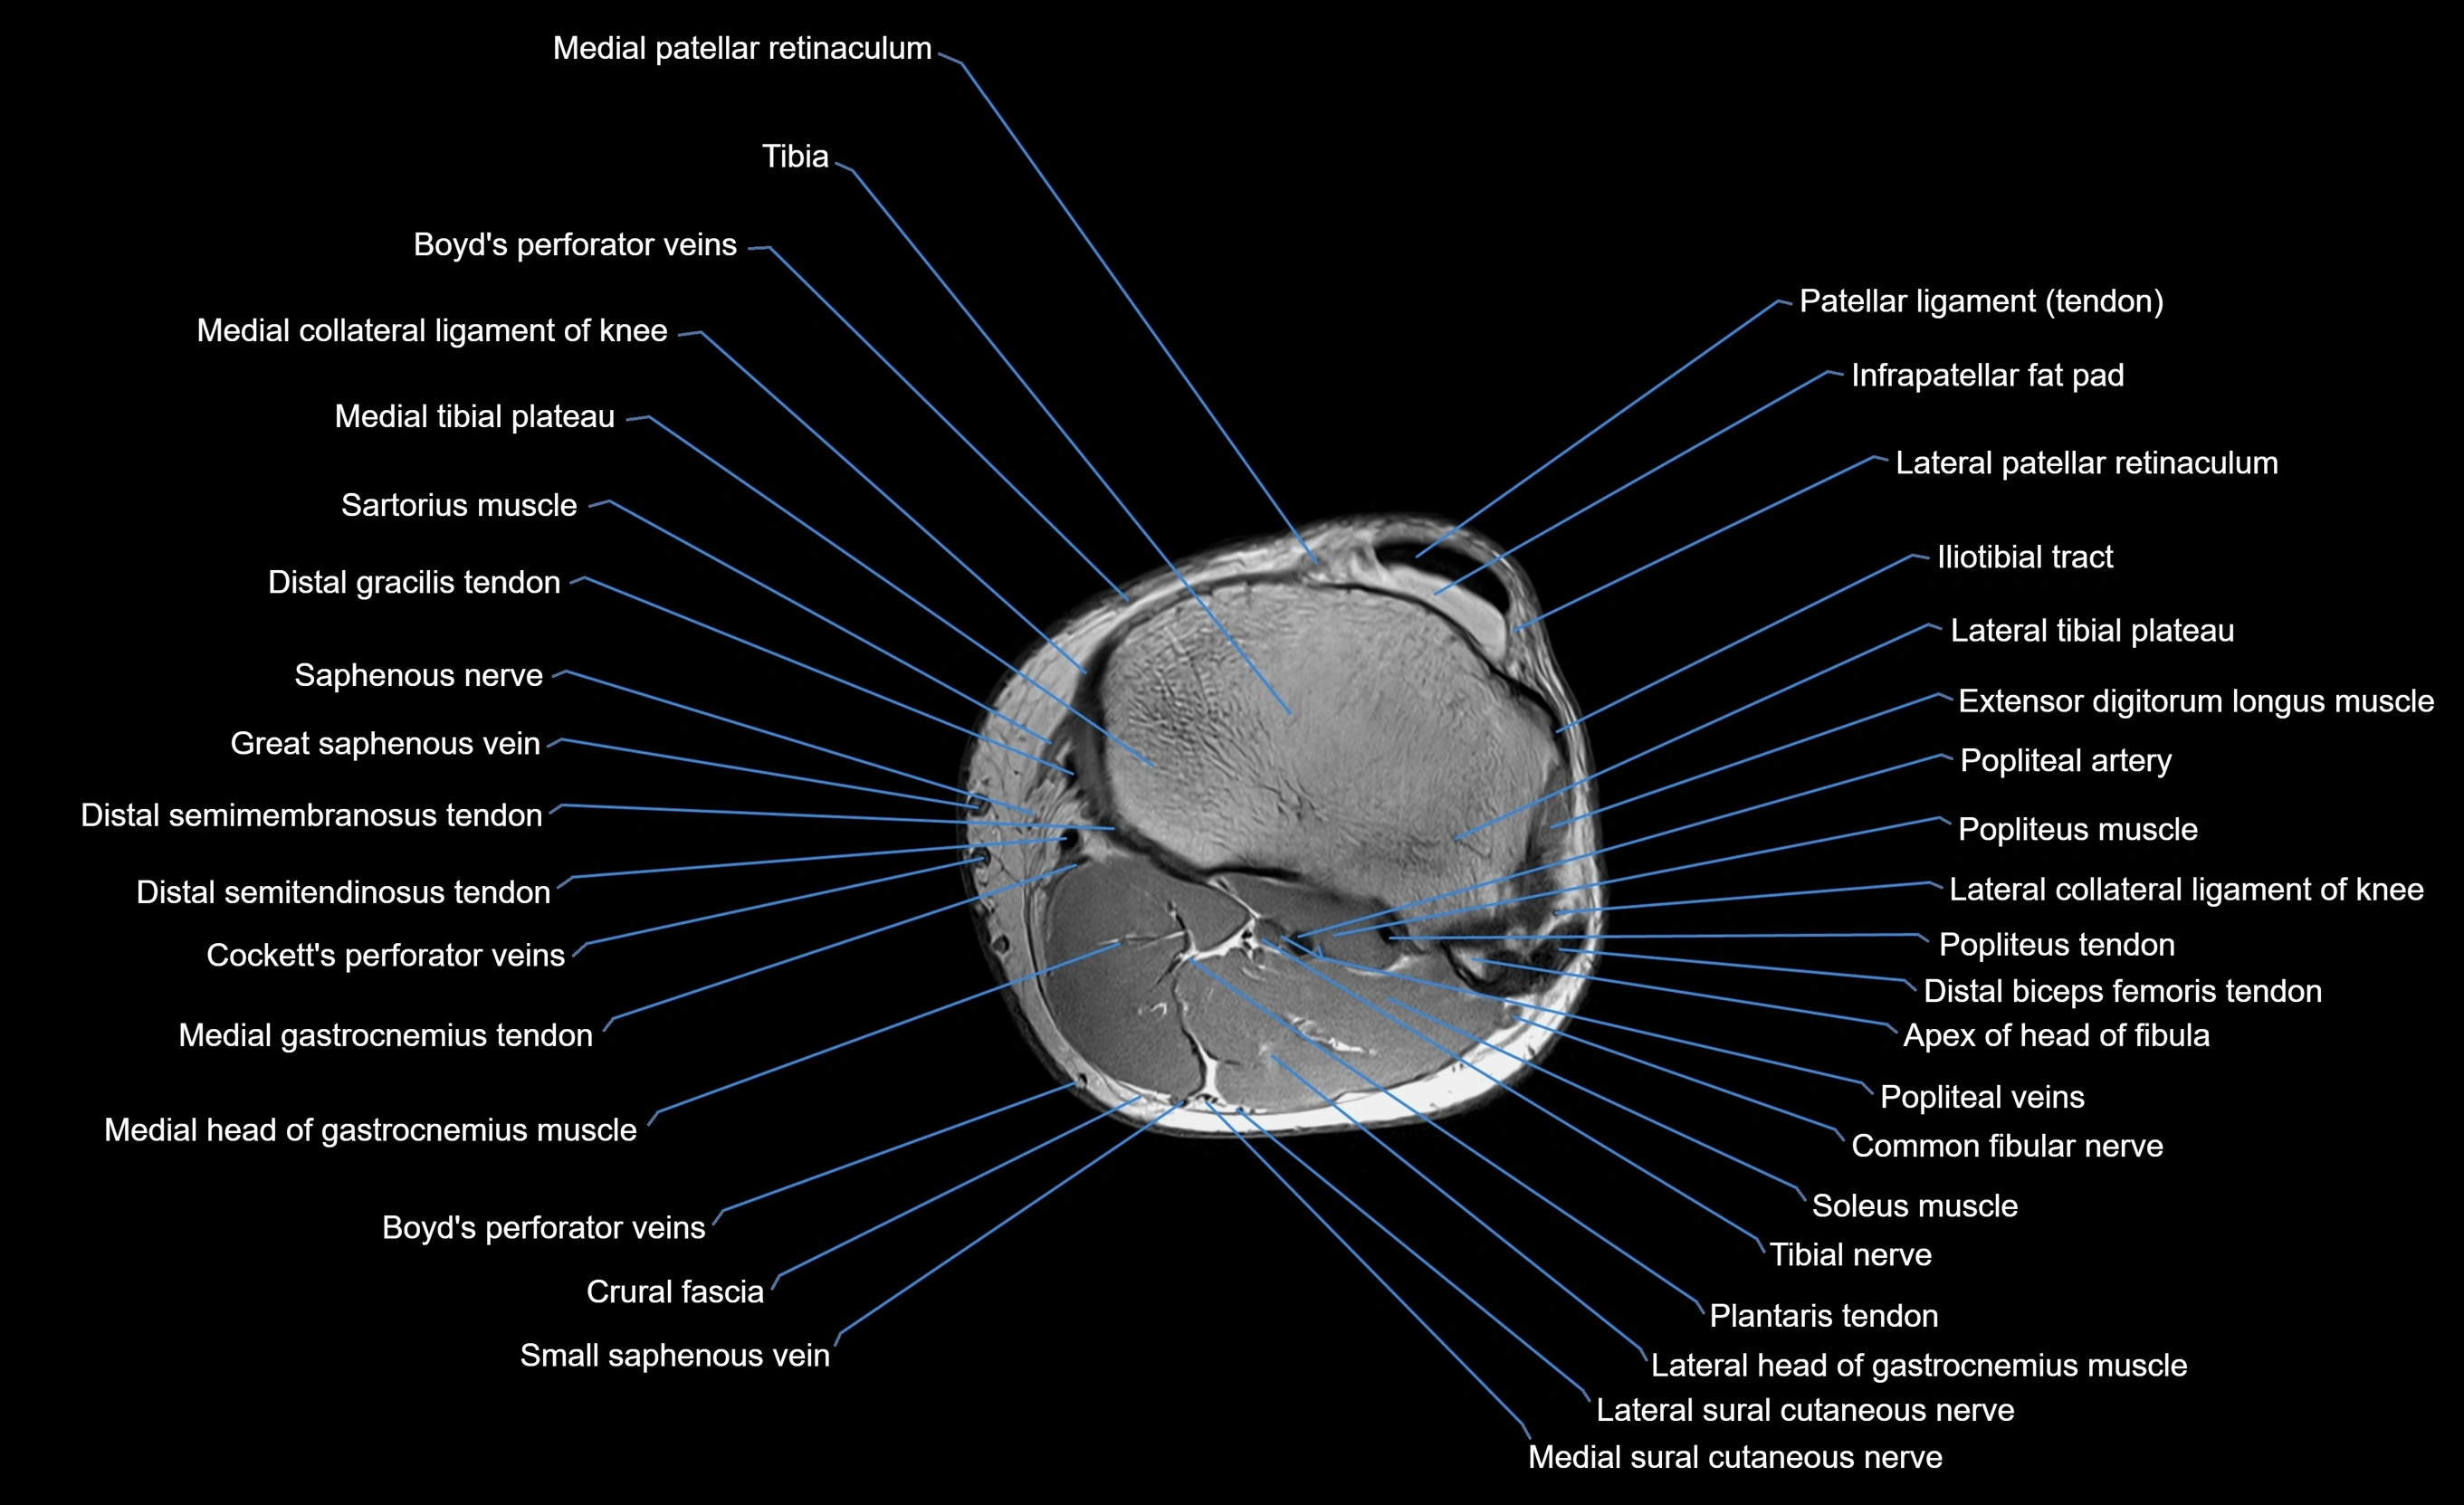

MRI image